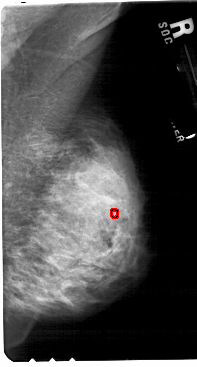

A_1845_1.LEFT_MLO

LEFT_MLO LINES 5491 PIXELS_PER_LINE 3136 BITS_PER_PIXEL 12 RESOLUTION 43.5 NON_OVERLAY

FILE: A_1845_1.RIGHT_MLO.OVERLAY

TOTAL_ABNORMALITIES 1

ABNORMALITY 1

LESION_TYPE CALCIFICATION TYPE PUNCTATE DISTRIBUTION CLUSTERED

ASSESSMENT 4

SUBTLETY 1

PATHOLOGY BENIGN

TOTAL_OUTLINES 1

BOUNDARY